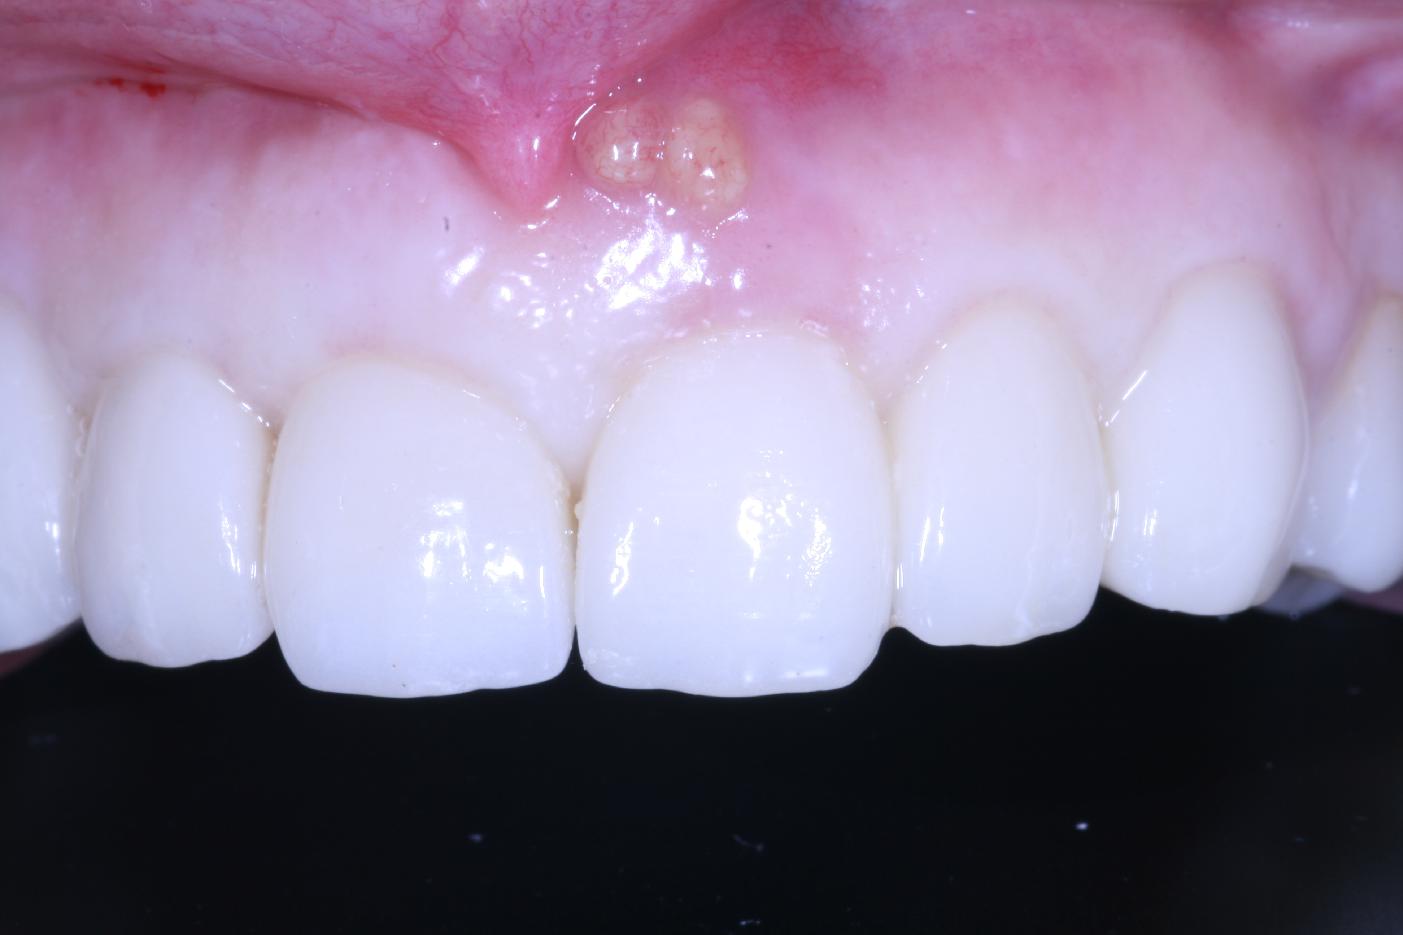

Longitudinal fracture on the root resected tooth 21 with visible buccal fistula